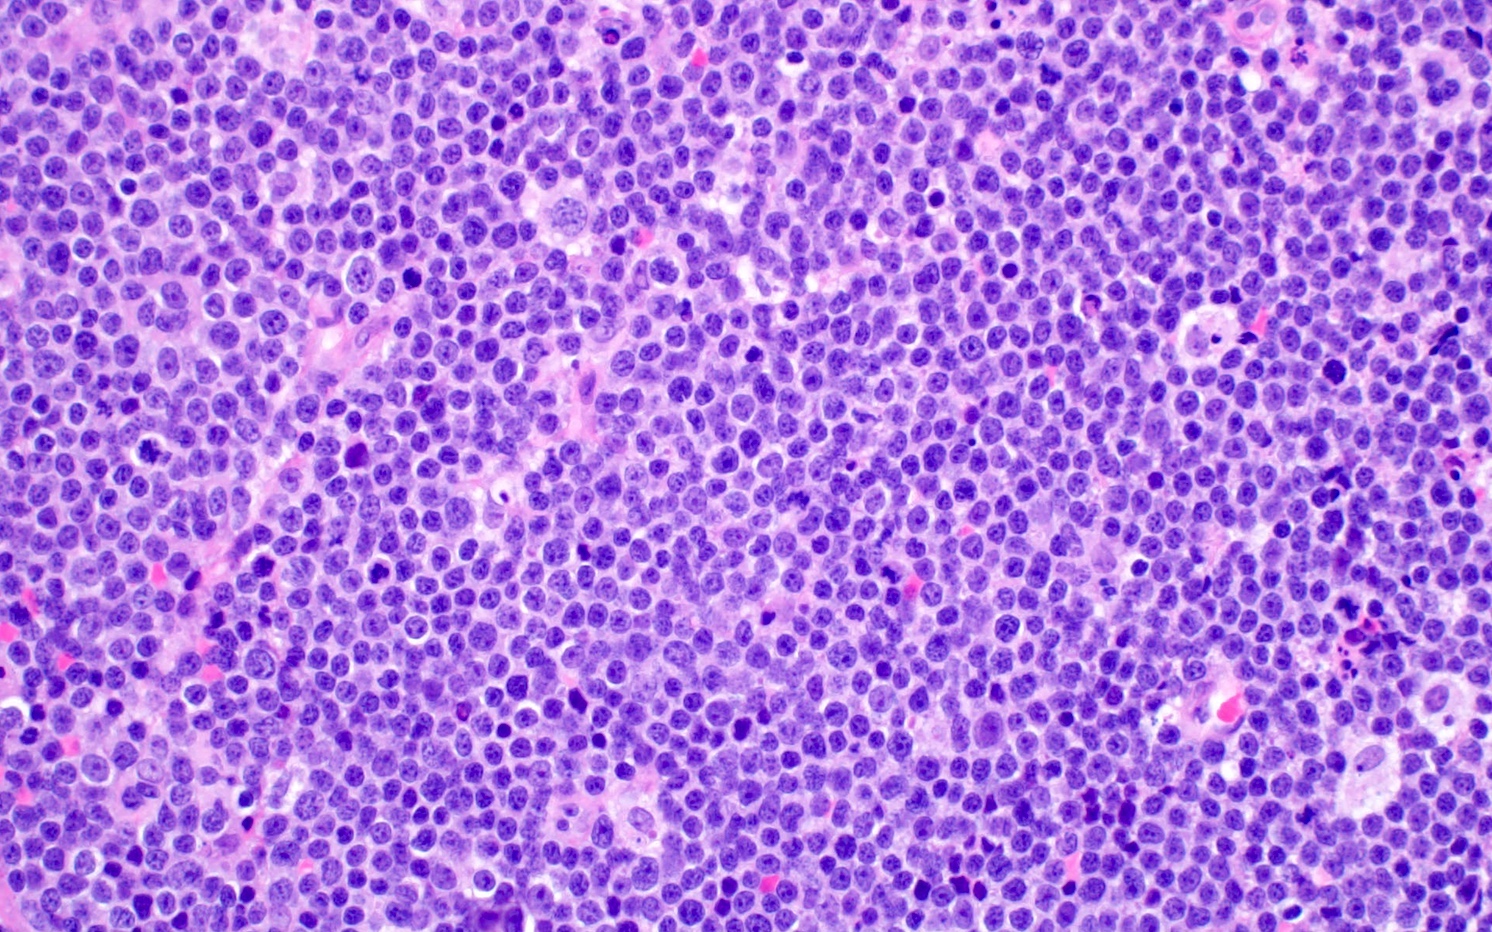

- Blastoid variant

- The growth pattern is usually diffuse

- Less frequently nodular pattern

- Starry sky appearance common in low power

- Intermediate sized cells

- Monotonous population

- Immature chromatin

- Scant cytoplasm

- High mitotic rate > 20 - 30/10 high power fields

- Resembles, in part, lymphoblastic lymphoma

Microscopic (histologic) images